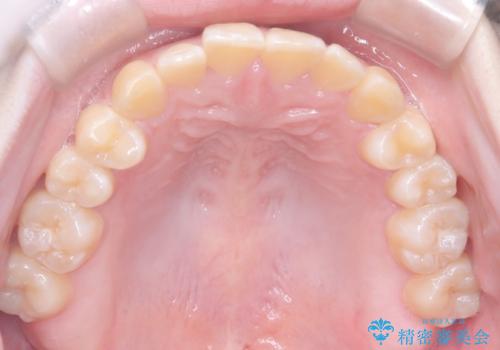

【インビザライン】オープンバイト。凸凹を治したい

- オープンバイトを主訴に来院されました。

インビザラインを用いIPRと遠心移動を行いオープンバイトと叢生の改善を行なっております。

前歯の叢生がわずかにありますが、追加アライナーの作成は希望されなかったため、歯を動かしていく動的治療は終了となりました。